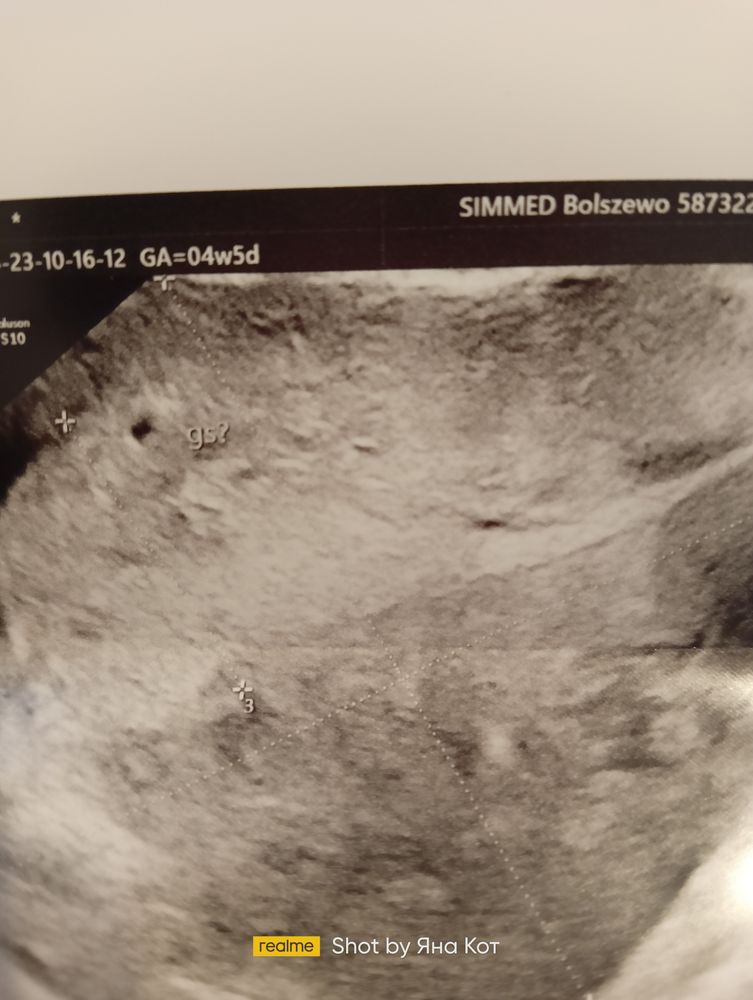

Сделали Узи. Плодного яйца не нашли хотя в Понедельник врач ставил под вопросом. Изображение Как так может бить